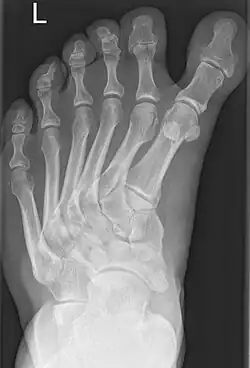

Polymetatarsia is a rare congenital malformation which is characterized by the presence of 6 or more metatarsal bones in the same foot. It is most commonly seen alongside polydactyly,[1] and it often appears between the fourth and fifth metatarsals or beside the fifth metatarsal.

Few cases of polymetatarsia not associated with polydactyly have been reported.[2]